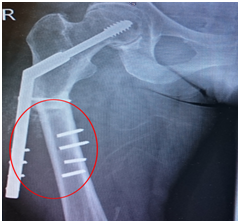

Figure 3 Conversion to dynamic hip screw with 10-hole plate.

Figure 6 Cephalomedullary nailing of fracture (denoted by a red circle).

Radiological evaluation of the right femur and pelvis showed an atypical subtrochanteric femur fracture of the right leg (Figure 3). She underwent a surgical operation the next day, and a two-hole plate was removed without removing the lag screw and was replaced using a DHS with an eight-hole plate (Figure 4). She started physiotherapy, and within few weeks, she was walking with a walking frame. She received regular follow-up radiological examinations. Her alendronate was discontinued, and she was started on teriparatide injections. Teriparatide is a synthetic parathyroid hormone that exists naturally in the body. She was undergoing this treatment when, in April 2015, she had another low-energy fall and was brought to the hospital with pain in the right thigh and was unable to bear weight. On radiologic examination, she had DHS implant failure and nonunion of the subtrochanteric fracture (Figure 5). She underwent an additional surgical procedure, and the DHS was removed. A long cephalomedullary nail was inserted (Figure 6). She started physiotherapy again. The patient is receiving regular outpatient follow-up and radiologic examinations. She is walking with a walking frame and continues to receive teriparatide injections.